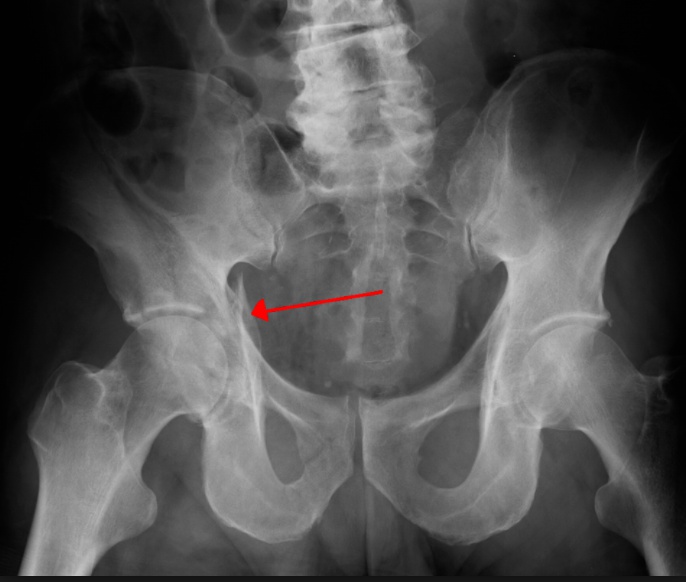

Pelvic

Pelvic fracture generally refers to a fracture of the acetabulum that occurs due to high-energy trauma in younger patients or a fall in older patients.

Patients with a pelvic fracture are unable to bear weight and may have a malrotated lower extremity.

A patient with major pelvic trauma who is hemodynamically unstable should receive a focused assessment with sonography for trauma (FAST).

If positive, the patient should be taken to the OR to address abdominal hemorrhage. Pelvic arteriography can be used if needed.

If negative, the patient should receive a diagnostic peritoneal aspirate. If positive, treat like positive FAST. If negative, extraabdominal hemorrhage should be controlled with pelvic stabilization and preperitoneal packing or pelvic arteriography.

A patient with major pelvic trauma who is hemodynamically stable should receive an abdominal CT scan.

If there are signs of active pelvic bleeding, pelvic arteriography should be performed. If there are no signs of active pelvic bleeding, the patient should be observed with serial examination.